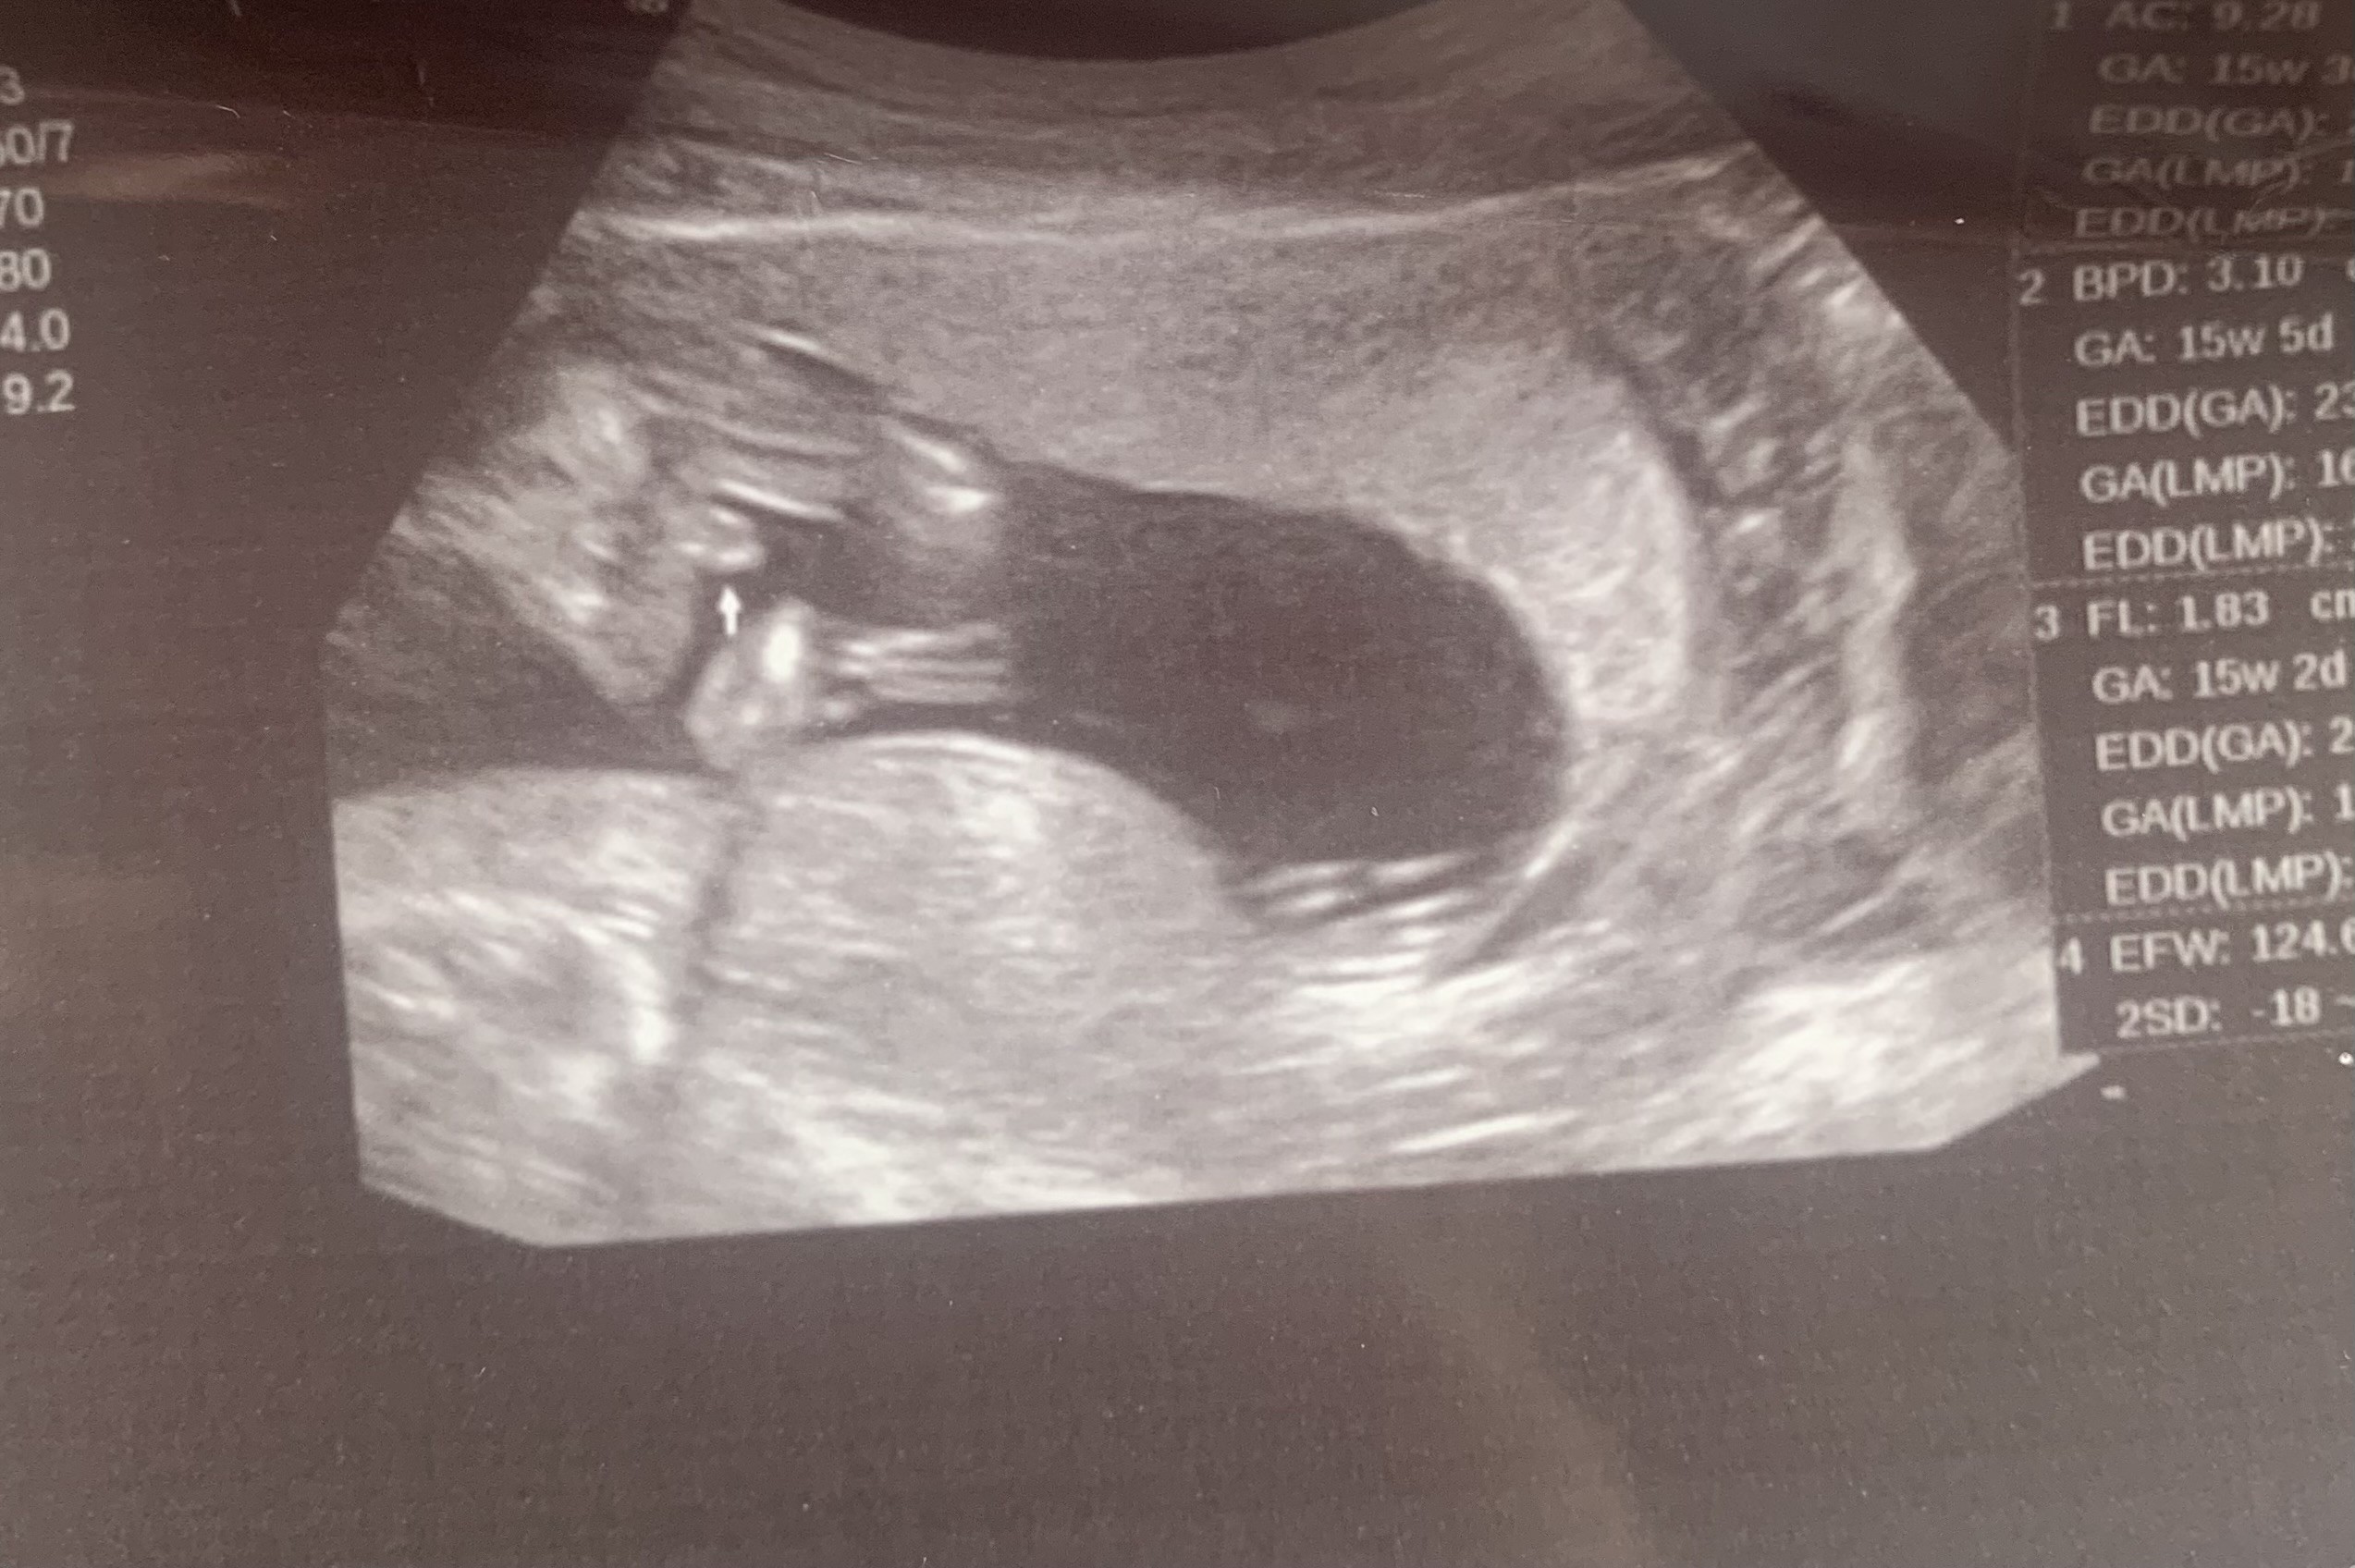

Dzień dobry USG płeć

Mam pytanie czy widać może na tym zdjęciu płeć dziecka 🤔

• IMG_20240810_160456.jpg

IMG_20240810_160456.jpg

110,5 KB · Wyświetleń: 651